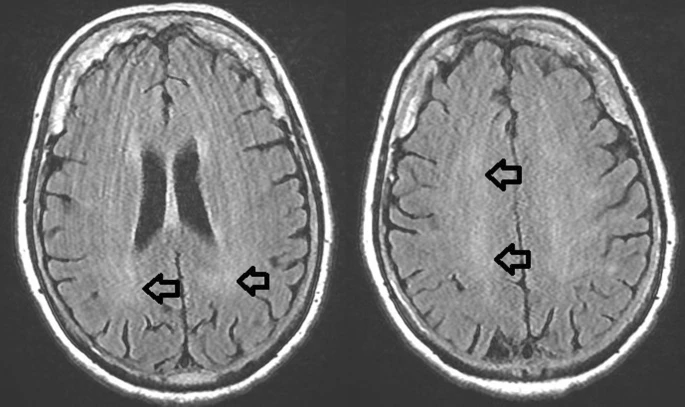

约 1% 的感染者会出现中枢神经系统受累情况,变现为脑炎或脑膜炎,并常常伴有颈部僵硬、精神错乱或癫痫。西尼罗河病毒一旦侵袭神经系统,患者死亡风险约为 10% 。几乎所有已报告的死亡患者均死于神经系统并发症 [2]。

神经受侵袭患者的脑部 MRI 检查

(箭头指示处:脑叶白质不规则高强度信号)

图源:参考资料 12